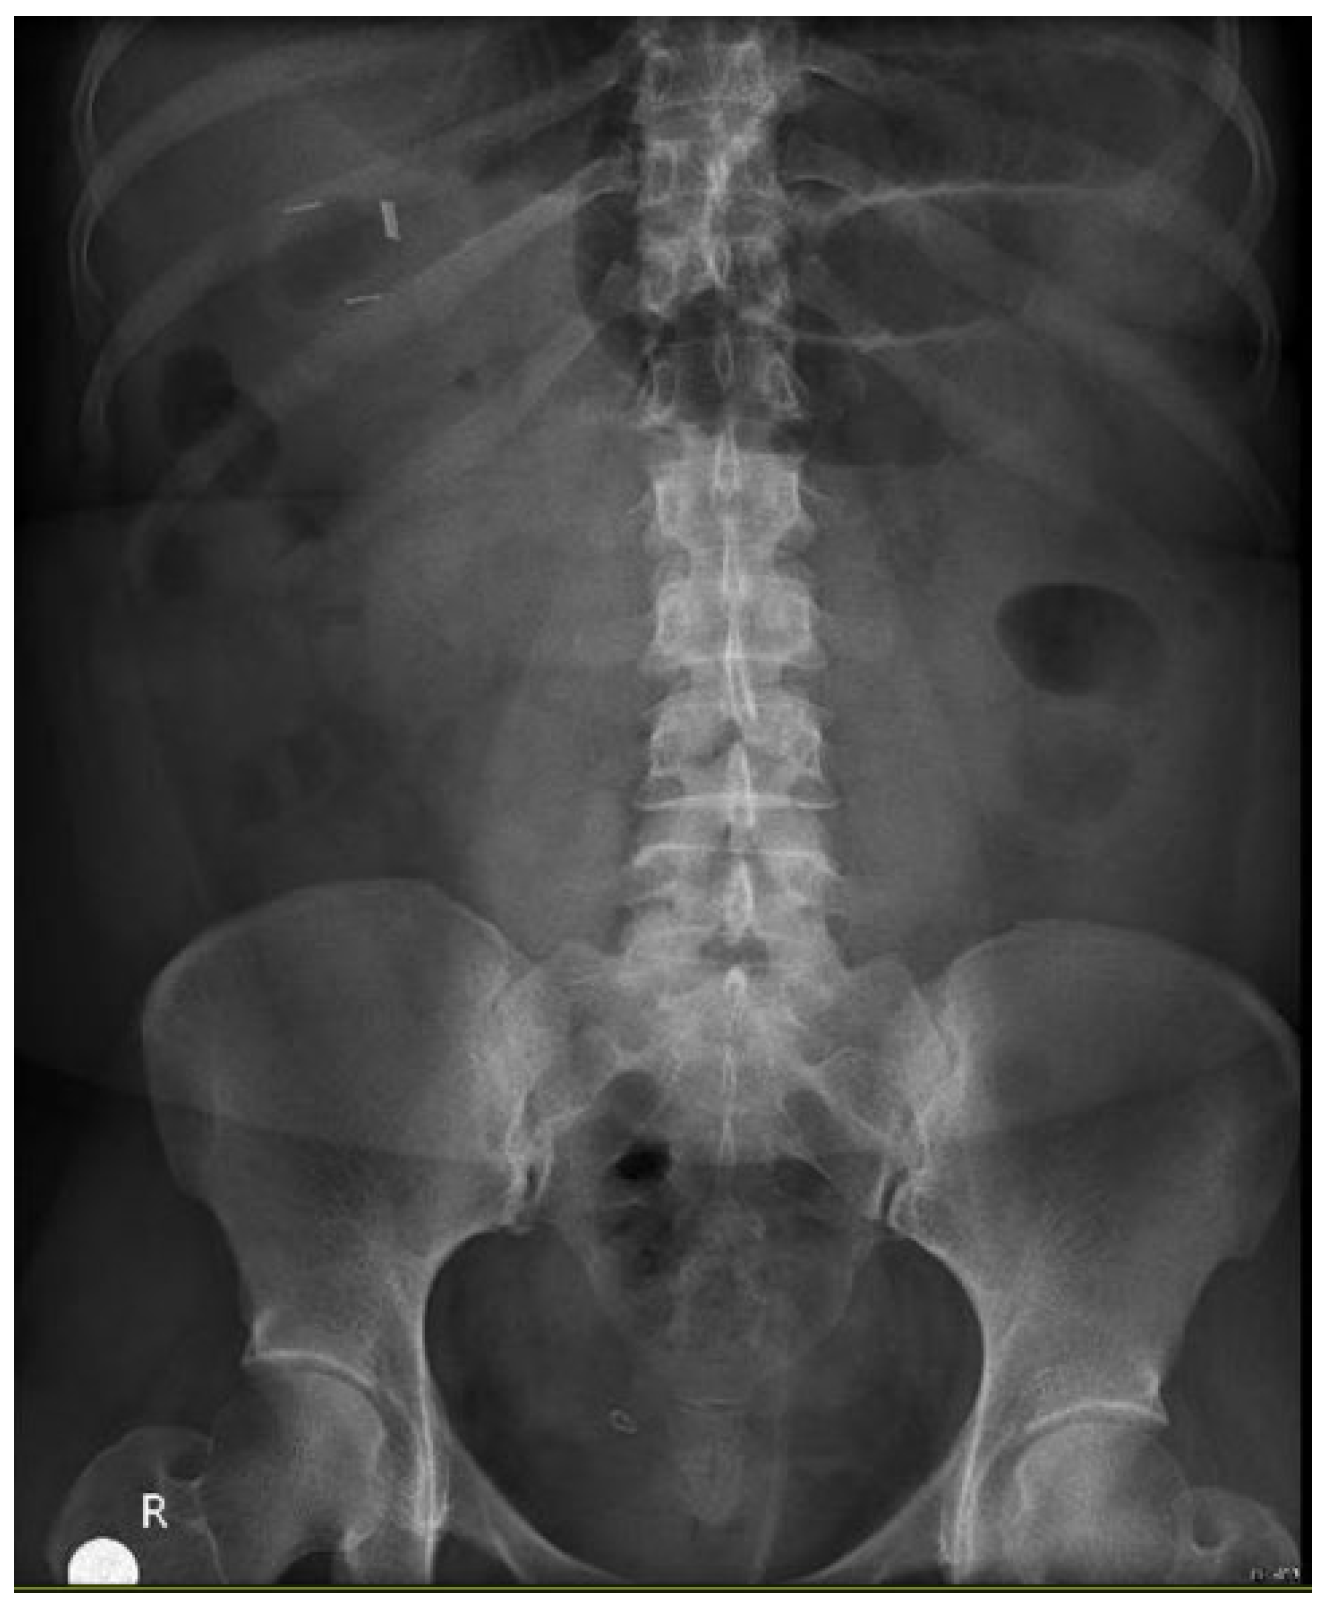

Patient arrives to the emergency room 48 hours after gastric sleeve surgery, she was admitted for abdominal pain referred to the left shoulder, a computer tomography (CT) was performed with evidence of leak at the gastroesophageal junction, a left subphrenic collection and pleural effusion of left predominance [Figure 1], she is taken to operation theatre and laparoscopic lavage and drainage is performed [Figure 2]. Treatment continues with IV antibiotics and parenteral nutrition. Thirteen days after re-intervention she presents deep venous thrombosis of the right lower limb and pulmonary thromboembolism of a segmental branch of the left lower lobe, she was managed with full anticoagulation and high flow cannula. She was then admitted to the intensive care unit (ICU) for 72 hours for observation. After stabilization is carried out, endoscopic management of the leak site with an Over-the-scope clip (OVESCO) is performed and mixed nutrition is installed, outpatient management is given with enteral nutrition for 4 weeks however the leak persists so after placement of vena cava filter, she is submitted for revisional Roux en Y gastric bypass [Figure 3]. Patient is discharged at 72 hours with complete resolution of the fistula, current follow-up at 4 months has been uneventful.

Figure 1. Computed tomography showing liquid collection near the spleen and leak near the gastroesophageal junction.